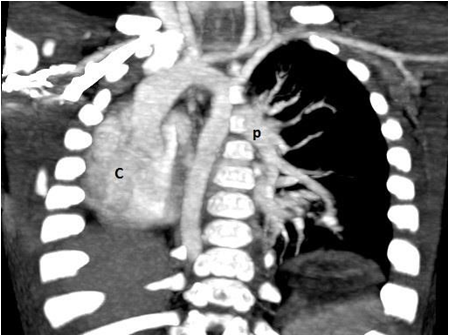

AUL, Absent Lt Upper Lobe; LLB,  Lt. Lower Lobe Bronchus;   ALL, Aberrant artery from the aortic arch supplying Lt. Lower Lobe;  L, hyperinflation of contralateral lung; LLL, Lt. Lower Lobe.

With a suspicion of Lt lung agenesis, a high resolution contrast enhanced CT scan was ordered. This showed agenesis of the Lt upper lobe, a rudimentary Lt lower lobe and an aberrant artery from the aortic arch supplying the left lower lobe. This was consistent with a Type 3 of lobar agenesis, and hypoplastic, ipsilateral pulmonary artery with normal bronchus of the lower lobe. An aberrant systemic arterial supply to lower lobe was an additional finding.

At 4 months of age, the child underwent a left thoracotomy and the aberrant artery from aorta was re implanted into the pulmonary artery, thus restoring the pulmonary blood supply to the left lower lobe. Should this procedure was not possible, the child would have had removal of the left lower lobe.

6 months after the left thoracotomy, the chest X Ray show well expanded, but smaller left lung. As the infant was showing signs of symptomatic gastro esophageal reflux disease, we performed a Nissen type fundoplication as an open procedure, successfully. Child was followed up regularly and is seen gaining weight normally and without any respiratory symptoms at 6 years of age.